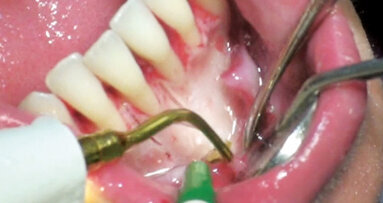

Dvě kazuistiky přímé kompozitní dostavby frontálních zubů s pomocí kompozitního materiálu Charisma Topaz (Heraeus Kulzer). Zkrácená verze – celý článek naleznete na www.stomateam.cz, nebo v časopise StomaTeam 5/2016 (pozn. red.).

Frontální výplně jsou velice individuálním typem ošetření, při němž terapeutické možnosti závisí především na velikosti defektu a estetických požadavcích pacienta. Přestože nepřímé keramické náhrady jsou vysoce kvalitním univerzálním „kouzelným“ výstupem, který umožňuje vložit estetické a funkční problémy do rukou zubního technika, vyžadují obvykle výrazně masivnější základní konstrukci než přímé kompozitní výplně a jsou také výrazně dražší. Kromě aspektu nákladů však přímé výplně skórují i z hlediska přístupu „jedné návštěvy“, tj. že pacient nepotřebuje žádnou provizorní náhradu a může jednoduše odejít domů s definitivní výplní. V zásadě totéž je možné se systémem Cerec, ale požadavky na zbytkovou hmotu zubu a náklady zde zůstávají.